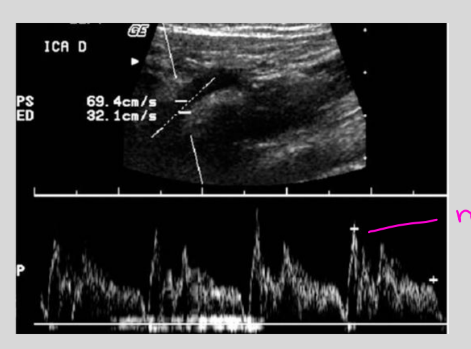

Bigeminy: irregular beat that

is followed by a normal beat